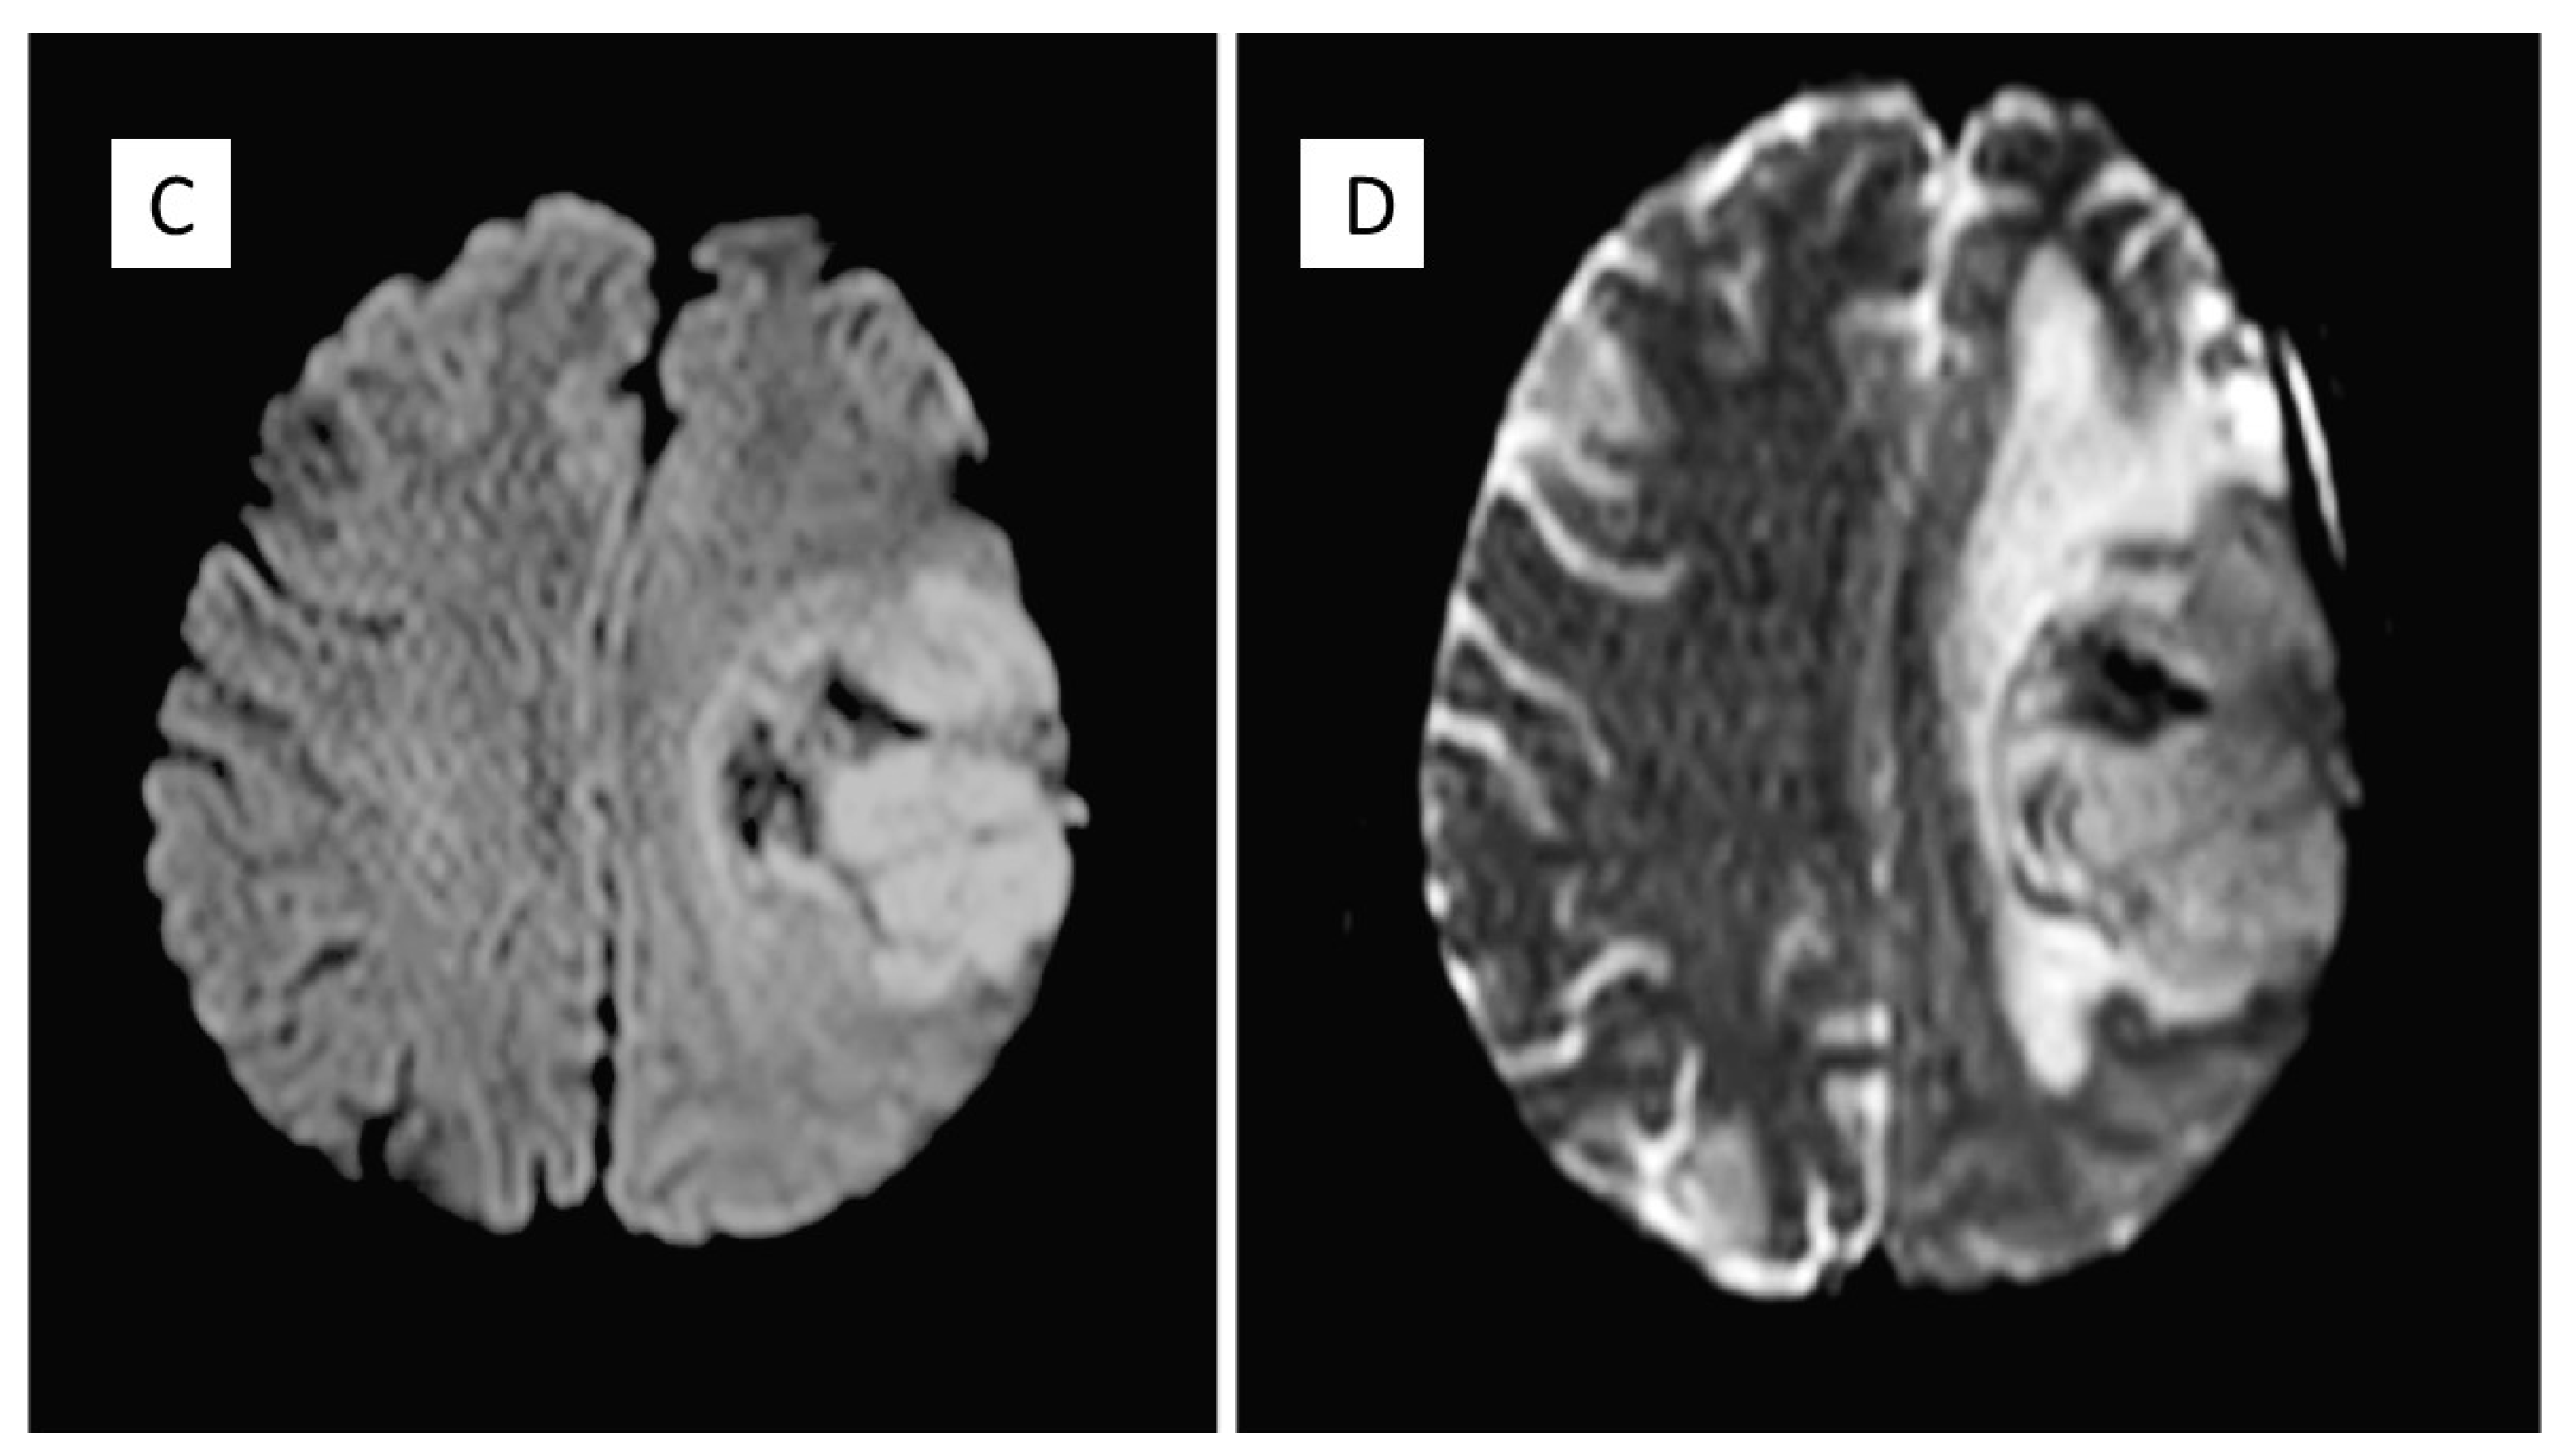

| 2015 | Headache | Recurrence of PM | Neurosurgical removal |

| 2020 | Headache, sleep disturbances and functional symptoms | Recurrence of PM | Tumour excision |